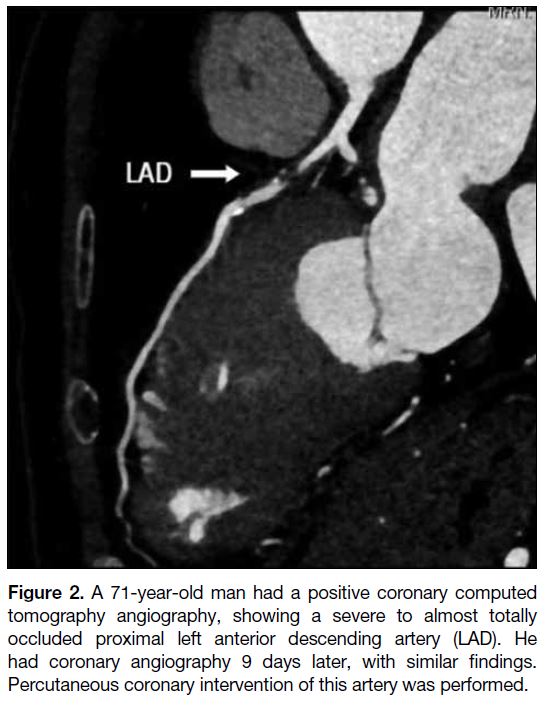

Ten patients (29.4%) with a positive CCTA result (≥50%

of stenosis on CCTA) were admitted to medical wards for

further assessment by cardiologists (Figure 2). They had

Figure 2. A 71-year-old man had a positive coronary computed

tomography angiography, showing a severe to almost totally

occluded proximal left anterior descending artery (LAD). He

had coronary angiography 9 days later, with similar findings.

Percutaneous coronary intervention of this artery was performed.